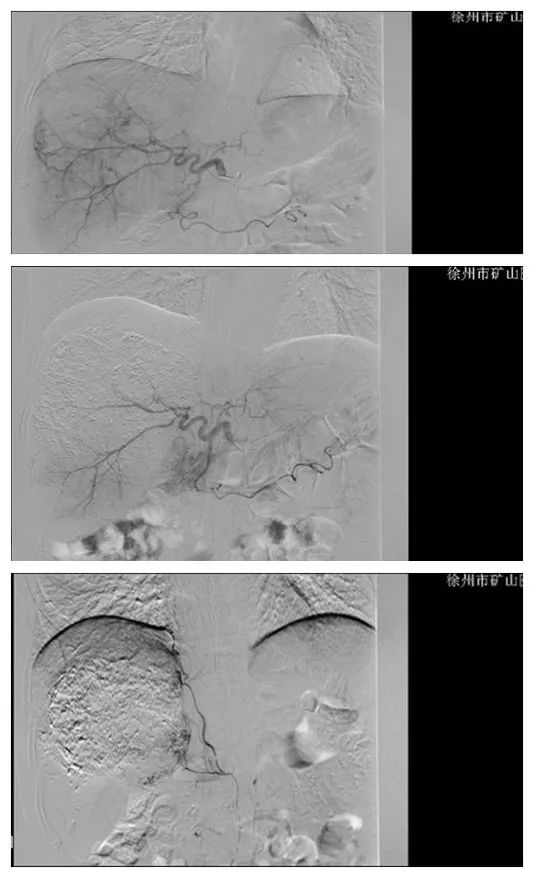

入院后,行上腹部增强CT提示:肝右叶占位性病变。考虑原发性肝癌可能,肿瘤体积较大,已是中晚期症状,患者已失去手术外科切除机会。

术前CT

经过与家属商量后,介入科施宏飞副主任医师为其行肝动脉化疗栓塞术(TACE),经过4个月两次栓塞后,肿瘤体积明显缩小,患者生活质量明显提升。

2个月后复查CT

4个月后复查CT